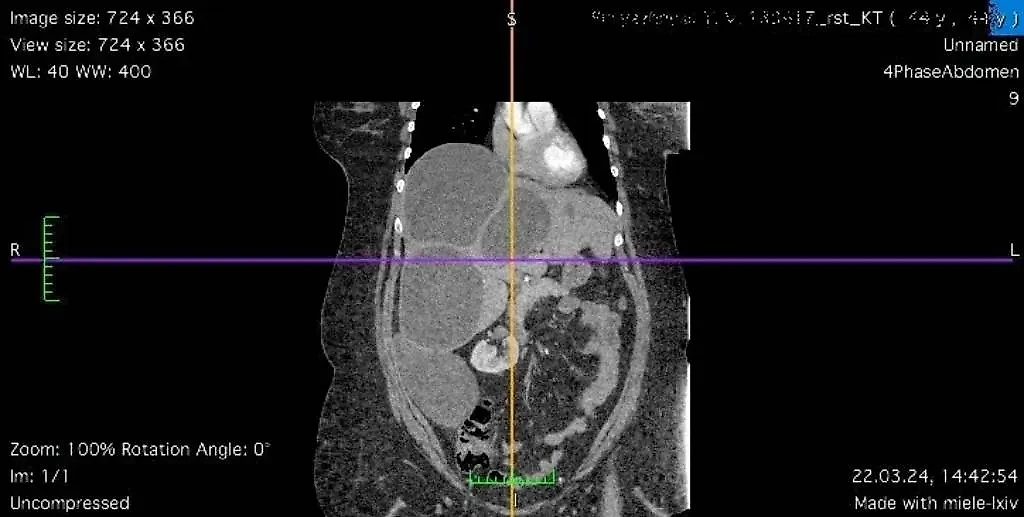

Снимок, полученный при проведении спиральной компьютерной томографии у пациентки из Луганска, которую спасли ростовские врачи. Фото © РостГМУ

"Обнаружен значительный объём поражения печени эхинококкозом — практически всей правой и части левой доли. Четыре крупных эхинококковых кисты заместили более 50% ткани печени", — отметил доктор медицинских наук, профессор, завкафедрой оперативной хирургии и топографической анатомии РостГМУ Юрий Хоронько.